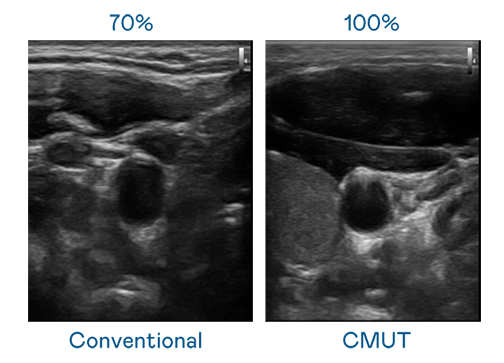

CMUT 技術是一種用電容式微機電元件來產生超音波訊號的技術。與傳統 PZT 壓電式技術相比,CMUT 頻寬增加 30%,更寬頻的超音波訊號讓影像解析度大幅提升,是實現高影像品質醫療超音波掃描、促進精準醫療發展的關鍵技術。

超音波影像的解析度高低,首先取決於探頭能發出的訊號頻寬。yd12399云顶 CMUT 可提供高清晰的超音波訊號,提供高頻寬、高靈敏度、影像紋理細節更高的超音波影像,協助醫護人員縮短影像判讀時間及利用精準的醫療影像進行診斷。